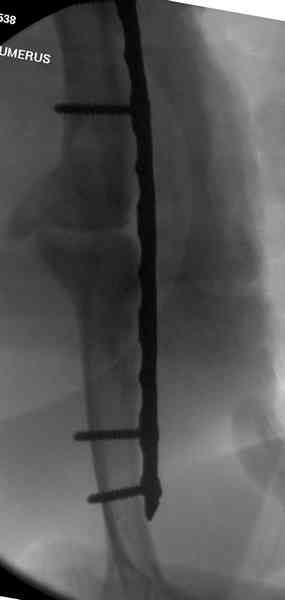

Как видно из выступлений коллег, способы фиксации

ложного сустава плеча могут быть различными, кто-то предпочитает аппаратом Илизарова (Соломин), пластинами (Волна) или интрамедуллярным гвоздем (Челноков).

Когда разбирался случай на сайте, и у нас была больная с похожей патологией, ложный сустав после поперечного перелома, леченного год назад где-то и кем-то в другом месте.

Первичную пластину убрали недели 6 назад из переднего оригинального доступа, и из-за подозрительности тканей вокруг пластины, решили провести реконструкцию поэтапно.

Хотя сам не стороннник применения более массивных

имплантов для плеча, но для этого случая сделали

исключение. На снимке 4А диаметр мягких ткани около 20 см, при весе больной более 135 кг, и также выступление Андрея Волны подстегнуло к применению более массивной 4.5 мм локинг пластины.